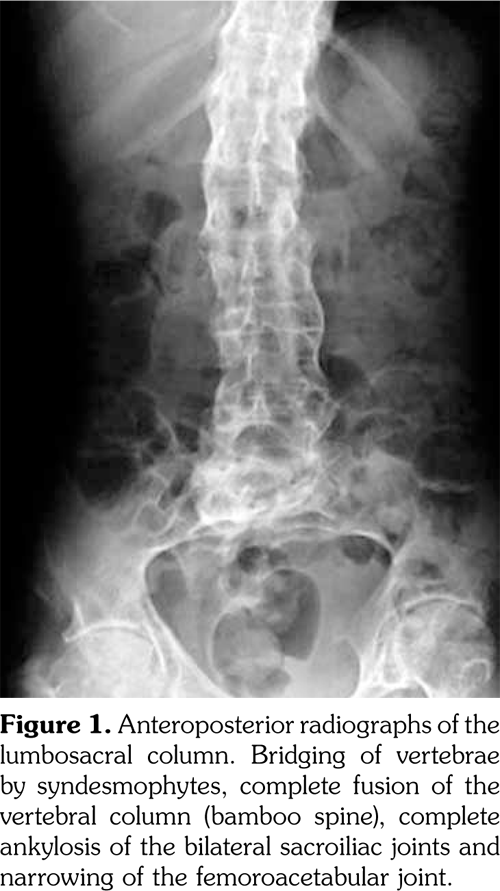

A 61-year-old man was admitted to the department of neurosurgery with bilateral lower extremity weakness which had begun suddenly. The patient had a history of spontaneous falls at home on the same day. He soon developed back pain and weakness in his lower extremities. Magnetic resonance imaging (MRI) of the lumbar spine revealed L2 vertebral fracture and epidural hematoma extending from L2 to L4. The patient underwent decompression surgery for the epidural hematoma. After the surgery, the patient was consulted in our clinic to establish a rehabilitation program. There was a minor trauma in his history two weeks ago, and an ischemic stroke two years ago. The patient reported neck and back pain ongoing for many years, and morning stiffness lasting for 30 minutes. There was no history of night pain, arthritis, skin lesions or inflammatory bowel disease. Upper limb motor strength was normal. Lower limb motor strength examination revealed that bilateral hip flexor and knee extensor strength was 3/5, ankle dorsiflexor strength was 4/5, bilateral toe dorsiflexor strength was 3/5, extensor digitorum brevis muscle strength was 3/5, and ankle plantar flexor strength was 5/5. Sensorial examination was normal. Hoffman, Achilles clonus, and Babinski signs were positive bilaterally. There was no urinary or bowel incontinence. Lumbosacral and sacroiliac joint radiographies were compatible with bilateral grade IV sacroiliitis, syndesmophytes, squared vertebral bodies, and “bamboo spine” formation. Furthermore, radiography revealed anteriorposterior longitudinal ligament calcification and scoliosis (Figure 1, 2).